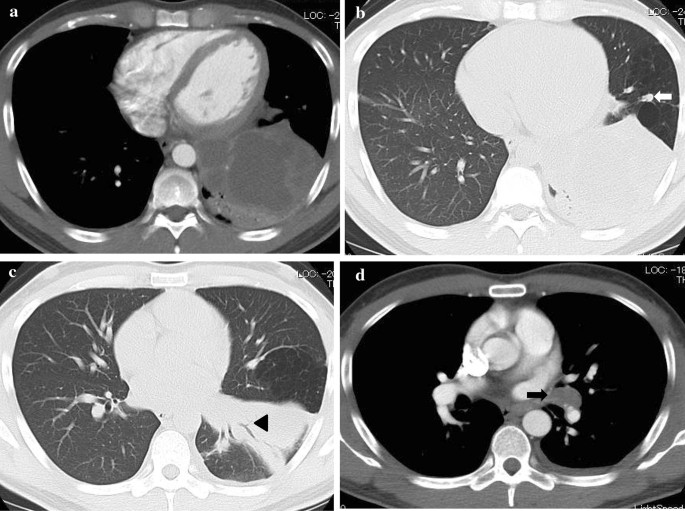

On admission, his vital signs were as follows: a body temperature of 36.6 °C, blood pressure of 120/66 mmHg, heart rate of 84 beats per minute, and a respiratory rate of 12 breaths per minute. The arterial oxygen saturation measured via pulse oximetry was 98% in the examination room. A physical examination including respiratory sound revealed no significant finding. Clinical laboratory tests showed that the patient had elevated C-reactive protein levels of 15.56 mg/dl (normal range, < 0.40 mg/dl) and his Aspergillus antigen test was positive (cut-off index of 3.5). Human immunodeficiency virus antibody and interferon-gamma releasing assay were negative. In addition, the β-D-glucan level decreased to a normal range (14.7 pg/ml). Chest X-ray and contrast-enhanced CT were performed on admission. Chest X-ray showed an infiltrative shadow in the left lower lung field (Fig. 1), and CT showed a massive lesion in the left lower lobe of the lung, emphysematous changes, ectatic bronchi, and a nodular lesion that was thought to contain a mucoid impaction within its lingular segment. The bronchus was disrupted proximal to the mass lesion of the left lower lobe (Fig. 2a–c). Consequently, bronchial atresia in the inferior and anterior basal segments of the left lung was suspected based on imaging findings. Since the presence of a malignant lesion could not be excluded, bronchoscopy was performed on day 2 after transfer to our hospital. An endobronchial ultrasound-guided transbronchial needle aspiration was performed on the small mass lesion near the left second carina (Fig. 2d). The disrupted bronchus could not be confirmed via bronchoscopy because the disrupted site was located too peripherally. Histopathological analyses revealed no malignant findings, but presence of a filamentous fungus was indicated in Grocott staining (Fig. 3). Although cultures did not detect any microorganisms, based on these findings, a lung abscess due to Aspergillus spp. was suspected. Therefore, VRCZ was reintroduced on day 9 after transfer. To perform treatment and confirm the suspected diagnosis of a lung abscess due to an Aspergillus infection, the patient underwent surgical resection of the lingular and basal segments of the left lung on day 22 after transfer. The abscess formation was macroscopically confirmed (Fig. 4), and histopathological examination revealed emphysematous changes and ectatic bronchi within the lingular and left basal segments (Fig. 5a, b). These findings were compatible with bronchial atresia [2], and no malignant lesions were confirmed. Although histopathological analyses did not reveal filamentous fungus, a tissue culture resulted in A. fumigatus growth. MEPM and intravenous VRCZ were continued for a total of 4 weeks and 3 weeks, respectively, and the patient was discharged on day 32 after transfer with continuing oral treatment with VRCZ. VRCZ was discontinued 5 months after the initiation of treatment because of poor medication compliance and the side effect of alopecia, and subsequent recurrence of the infection has not been confirmed.

Contrast-enhanced CT performed on admission revealing an abscess, emphysematous changes, ectatic bronchi, a nodular lesion that was considered a mucoid impaction of the lingular segment (arrow), and disrupted bronchus within the left lower lobe (arrowhead) (a–c). A small mass lesion near the left second carina (arrow) is also shown (d)